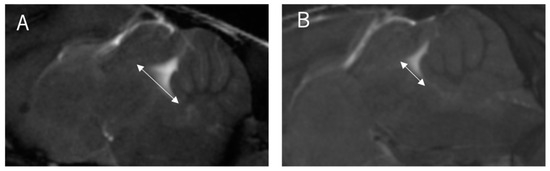

Two board-certified physicians and one senior author who specialized in the imaging of the CNS in laboratory animals independently measured the images of 30 mice (10 wild-type and 20 twy/twy mice) taken with the Time-SLIP technique 3 times. The examiners were blinded to the genotype of the mice. We defined the stir distance as the distance of CSF stirring in the sagittal plane within a single time period (3 s) in the fourth ventricle, where there is relatively more space, and three examiners took measurements 3 times for each mouse (Figure 2). Furthermore, the examiners also measured the antero-posterior diameter of the spinal cord and spinal canal on the MRI sagittal plane and calculated the canal stenosis ratio (CSR). (Figure 3) We examined the correlation between stir distance and CSR using Pearson’s correlation coefficient. Additionally, to eliminate the potential impact of respiration on the dynamics of CSF, the respiratory rates of wild-type and twy/twy mice were recorded and compared.

Figure 2. The distance of CSF stirring in the sagittal plane within a single time period at the bottom of the fourth ventricle. Stir distance (two-headed arrow shows stir distance). (A) Stir distance in 12-week-old wild-type mouse, (B) stir distance in 12-week-old twy/twy mouse.